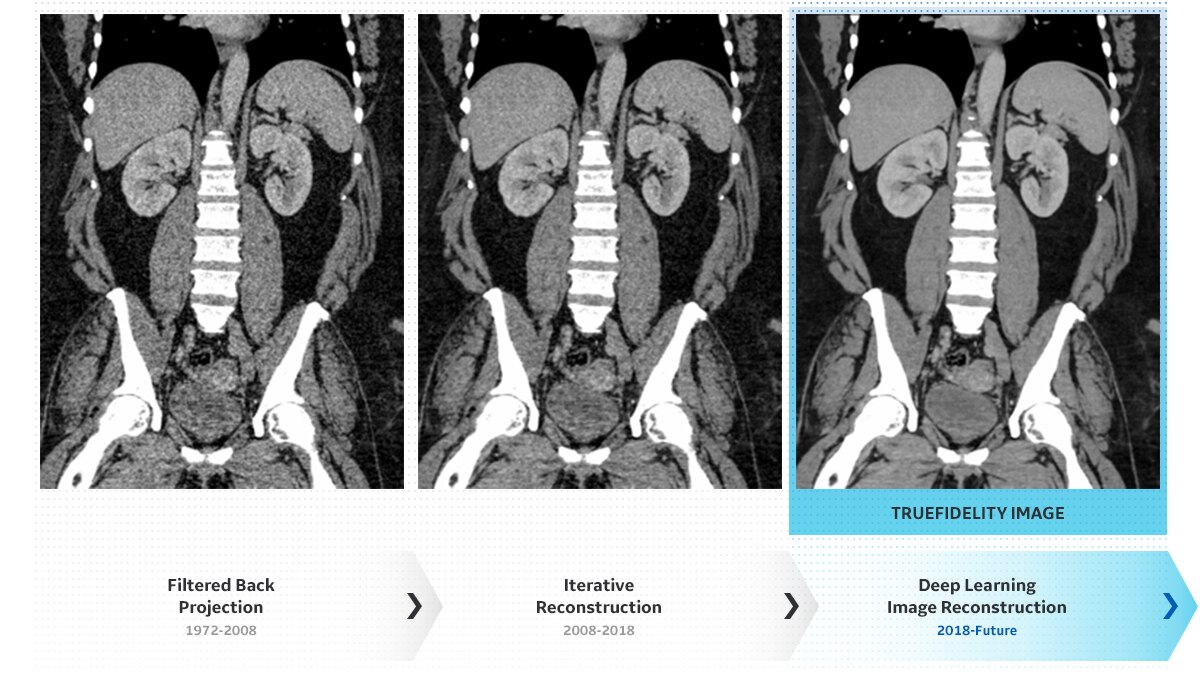

Introducing a new era

of image reconstruction.

FBP | 2.5 mm

ASiR-V 50% | 2.5 mm

Deep Learning Image Reconstruction | 2.5 mm

FBP

ASiR-V 50%

Deep Learning Image Reconstruction